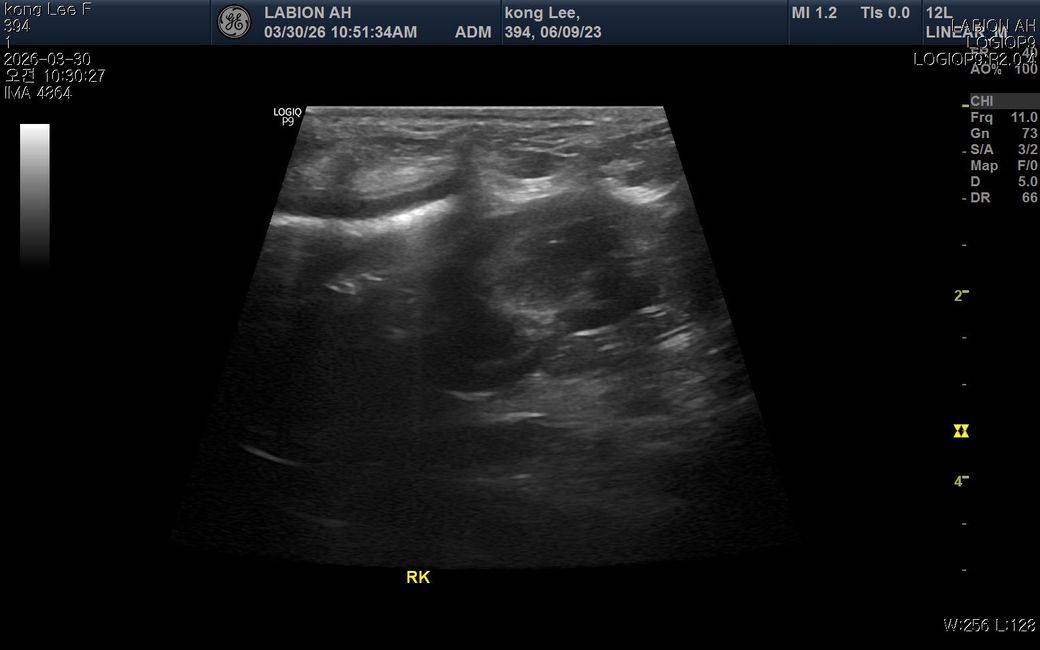

최근 황태 간식을 약 2~3개월 동안 매일 급여해왔고 염분이 느껴져 급여를 중단했습 니다. 이후 소변횟수가 살짝 감소하고 음수량이 평소보다 증가했고 동시에 밤잠이 줄고 낮에 무기력해졌습니다 원래 저녁에8시간정도 잤는데 중간에 한두번씩 깨거나 6시간으로 줄었고 밤잠이 줄어 낮에 좀 피곤해하는데 혹시 나트륨 섭취로 인해 체내 호르몬에 이상이 생긴걸까요? 2년전 슬개골 수술이력도 있지만 시기가 너무 겹쳐서 궁굼합니다

• 과도한 나트륨 섭취는 체내 전해질 불균형을 유발하여 음수량 증가와 배뇨 패턴 변화를 일으킬 수 있으며 이는 수면의 질을 저하시키는 직접적인 원인이 됩니다. 염분이 많은 간식을 장기간 섭취하면 신장에 부담을 주어 일시적인 대사 이상이나 다갈 및 다뇨 증상이 나타날 수 있고 이로 인해 야간에 갈증을 느끼거나 배변 욕구가 생겨 잠에서 자주 깨게 됩니다. 수면 부족이 낮 시간의 무기력증으로 이어지는 것은 자연스러운 현상이지만 증상이 지속된다면 단순히 식이 문제가 아니라 부신피질 기능 항진증과 같은 호르몬 질환 가능성을 배제할 수 없으므로 혈액 검사를 통한 수치 확인이 필요합니다. 슬개골 수술 이력과 직접적인 연관성은 낮아 보이나 통증으로 인한 불면일 수도 있으니 식단 조절 후에도 음수량이 줄지 않는다면 즉시 정밀 진단을 받는 것이 합리적입니다.